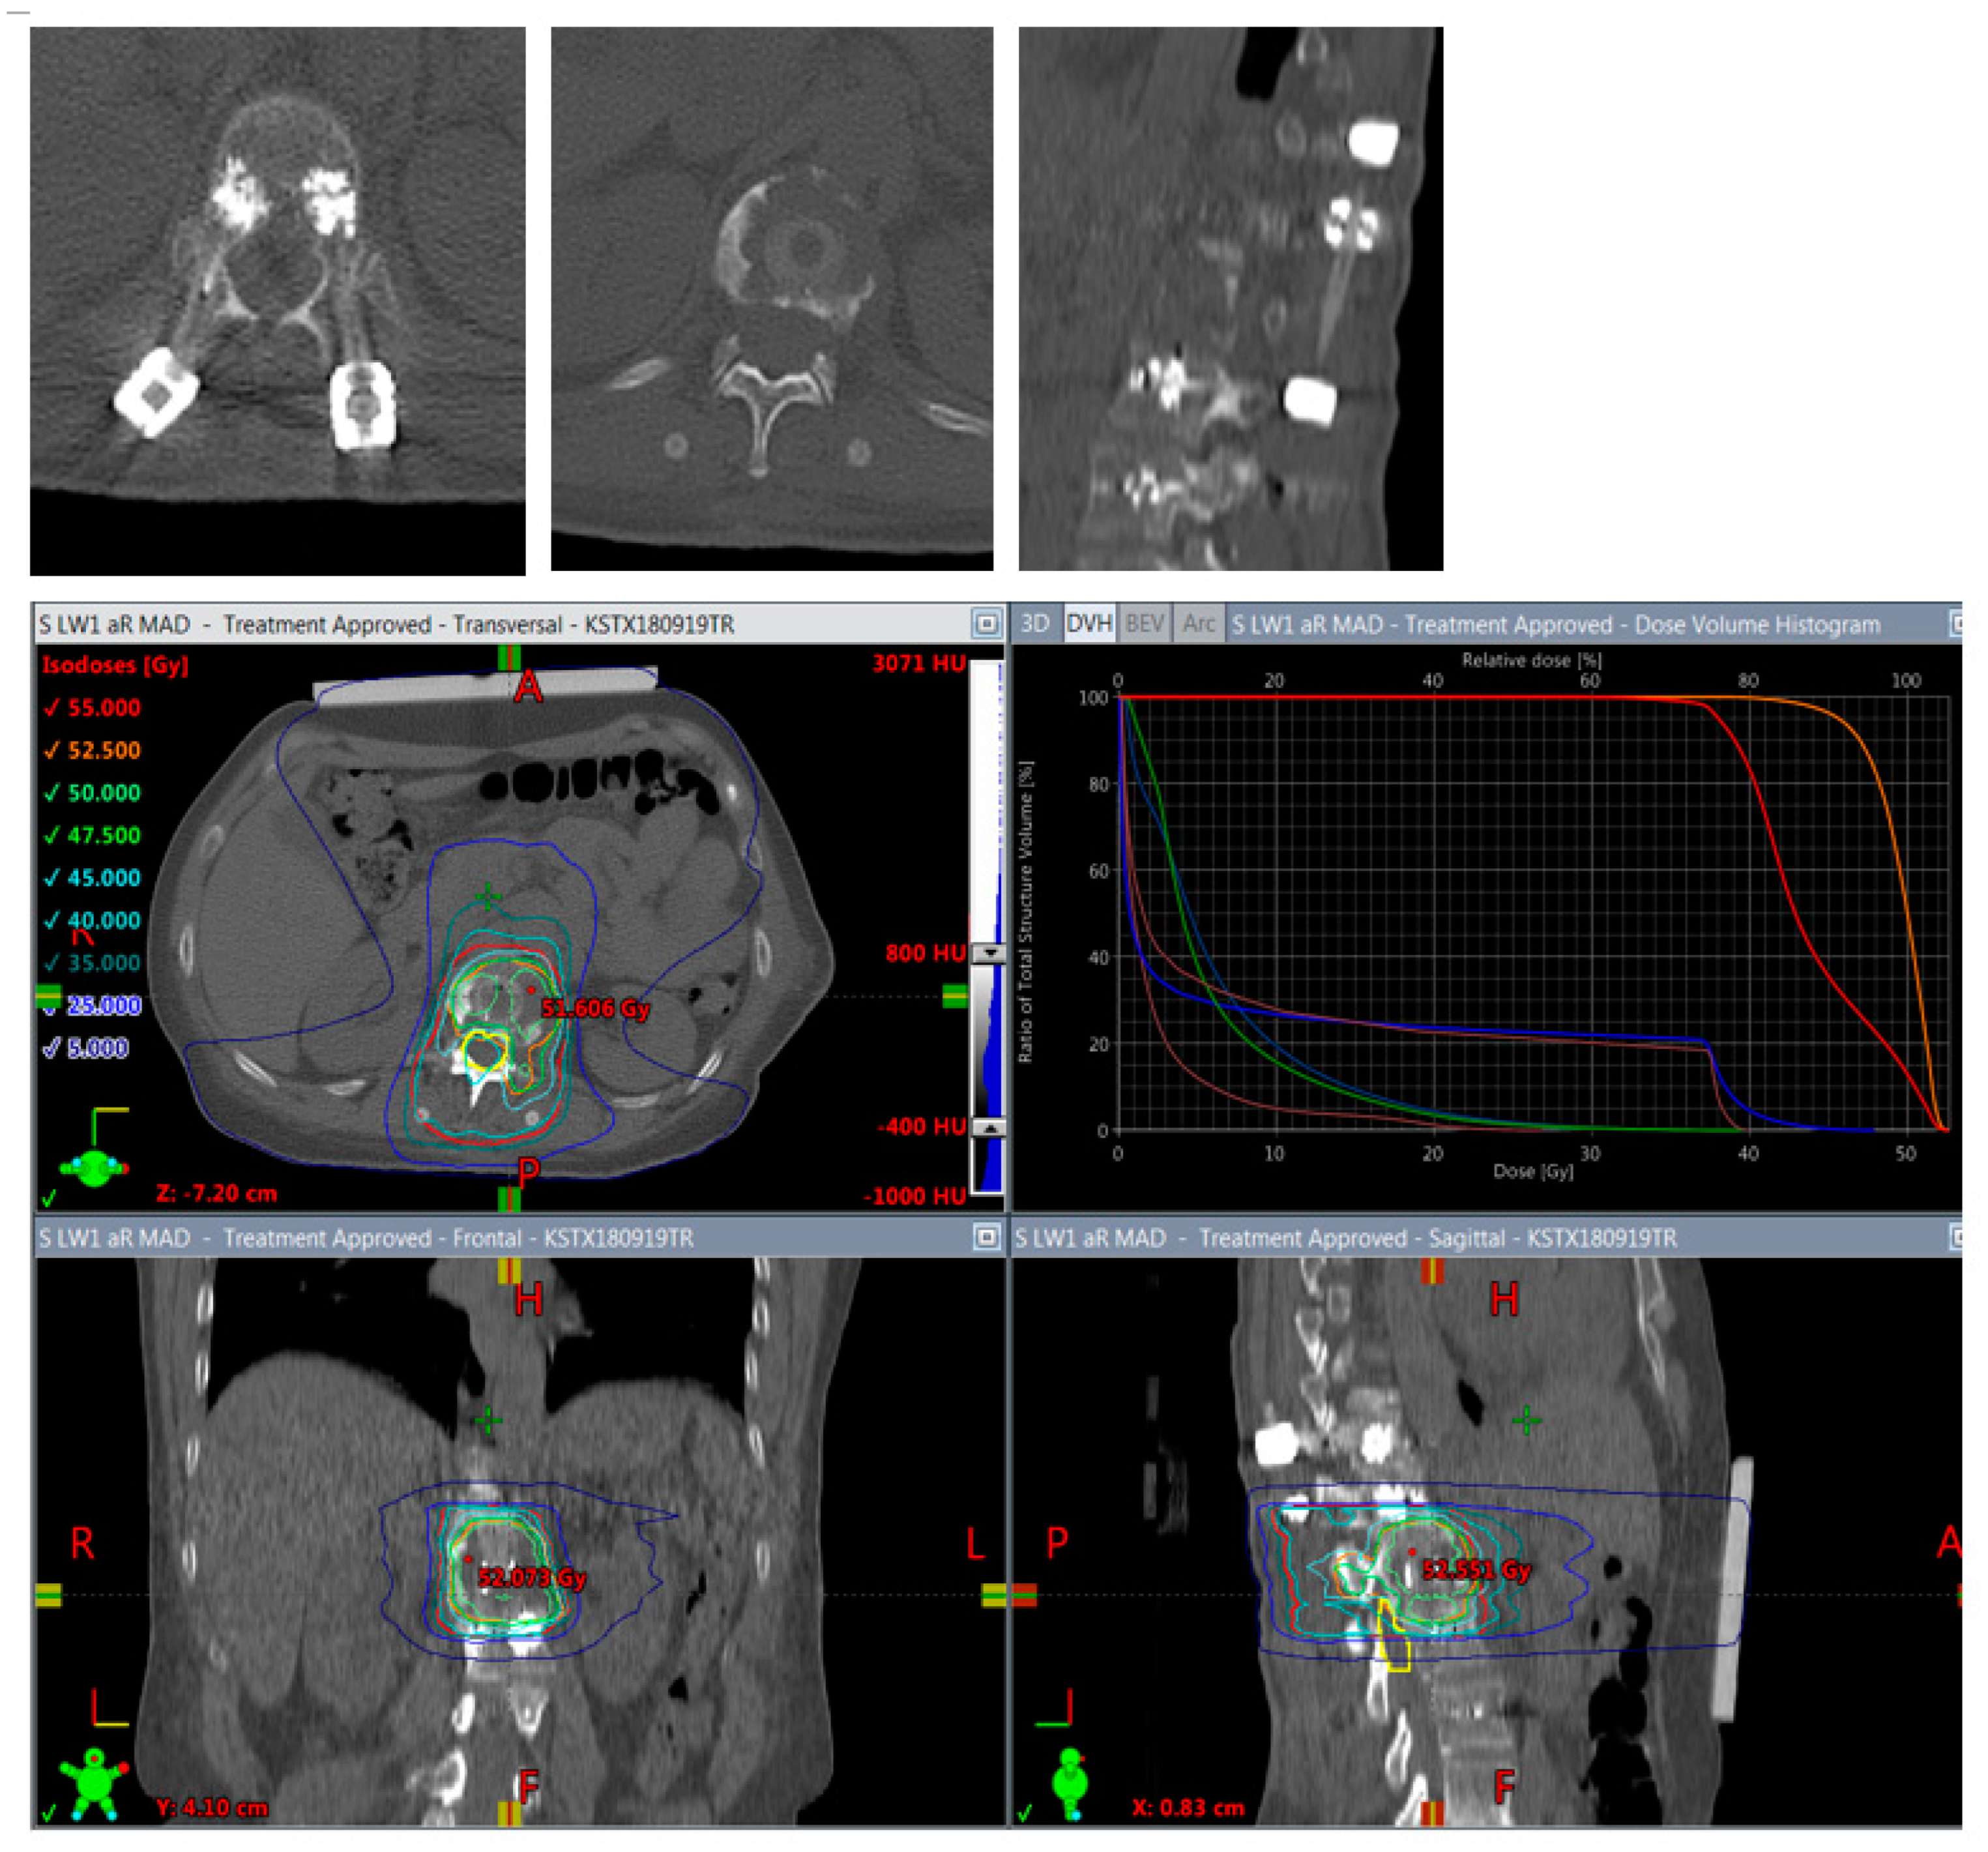

Figure 6.

Planning of postoperative radiotherapy: CFR-PEEK. Less artifacts allow smaller volume radiotherapy of 40/50 Gy á 2/2,5 Gy of the vertebral body alone. Dose escalation is possible and there is less risk to the spinal cord and others structures at risk.